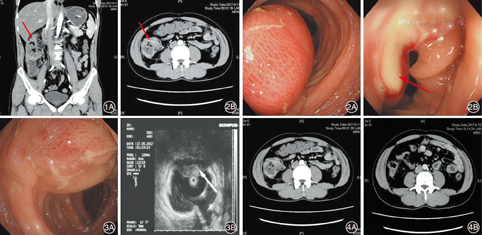

患者自患病以来体重减轻约8 kg。既往体健,否认乙肝、结核传染病史,无食物药物过敏史。入院查体示体温37.2℃,脉搏76次/min,呼吸19次/min,血压112/72 mmHg(1 mmHg=0.133 kPa),右侧腹触之饱满,压痛(+),肠鸣音6次/min,余无明显异常体征。本次复查血常规示WBC 13.8×109/L,N 74.1%,C反应蛋白(CRP)58.50 mg/L。结合患者症状及实验室检查,首先考虑肠道炎症,予左氧氟沙星0.5 g(1次/d)静滴抗感染及培菲康840 mg(2次/d)调整肠道菌群,后相关检查返回,包括大便常规+便潜血试验,大便培养+药敏,产毒素难辨梭菌检测等未见异常。次日肝胆胰脾及浅表淋巴结超声检查示脂肪肝,余未见明显异常。行胸部CT平扫示两肺散在少量间质性病变。入院第3天行全腹部CT平扫+增强,显示升结肠中上段及肝曲局部肠壁增厚伴异常强化,肠系膜根部多发淋巴结(图1);第4天行结肠镜检查见升结肠近肝曲有一长约10 cm的隆起灶,黏膜充血、水肿明显,表面糜烂,活检钳触碰质地较软,有波动感,活检见大量脓性分泌物流出(图2)。后病理示"升结肠"少量炎性肉芽组织。追问患者病史,发病前有不洁食物及贝壳类等食物食用史,且平素喜生食海鲜类食物,为排除因嗜食生冷引起的寄生虫感染损伤肠壁后导致肠壁脓肿的形成,行大便找虫卵及相关寄生虫抗体检测,结果无异常发现。经抗感染治疗及脓液引流,患者诉右侧腹部闷痛不适感明显减轻,查体腹部触诊饱满感及压痛消失,复查血常规WBC 7.4×109/L,N 61.1%,CRP 16.10 mg/L。入院1周后,患者腹痛症状消失,大便正常,复查肠镜见升结肠中段黏膜隆起灶,范围较前明显缩小,长3~4 cm,表面呈斑点状充血糜烂,质软,无波动感,用注射针穿刺后未能抽得液体,用12 mHz超声探头探测见该处肠壁层次清楚,黏膜层明显增厚,呈偏低回声,未见明显无回声区域或低回声区域(图3),遂予出院并嘱左氧氟沙星0.5 g(1次/d)口服。

出院后2周电话随访,患者无腹痛,门诊复查血象无异常。出院1个月后复查腹部CT示升结肠中上段及肝曲局部肠壁轻度增厚、强化,较之前明显好转(图4)。